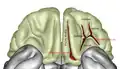

Cerebrum. Inferior view. -

Cerebrum. Inferior view. Deep dissection.